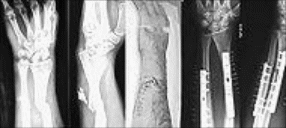

Основные принципы лечения переломов не изменились с эпохи античности, хотя современная хирургия и позволила восстанавливать анатомическую структуру костей при сложных, вколоченных, многооскольчатых переломах, переломах, неправильно сросшихся, без восстановления нормального положения кости, и многих других видах травм.

перелом шиловидного отростка лучевой кости - перелом Коллеса.

переломе локтевой кости в верхней трети и вывихе головки лучевой кости с повреждением ветви лучевого нерва перелом Монтеджа,

перелом лучевой кости в нижней трети с разрывом дистального радио-ульнарного сочленения и вывихом в этом суставе - перелом Голеацци.